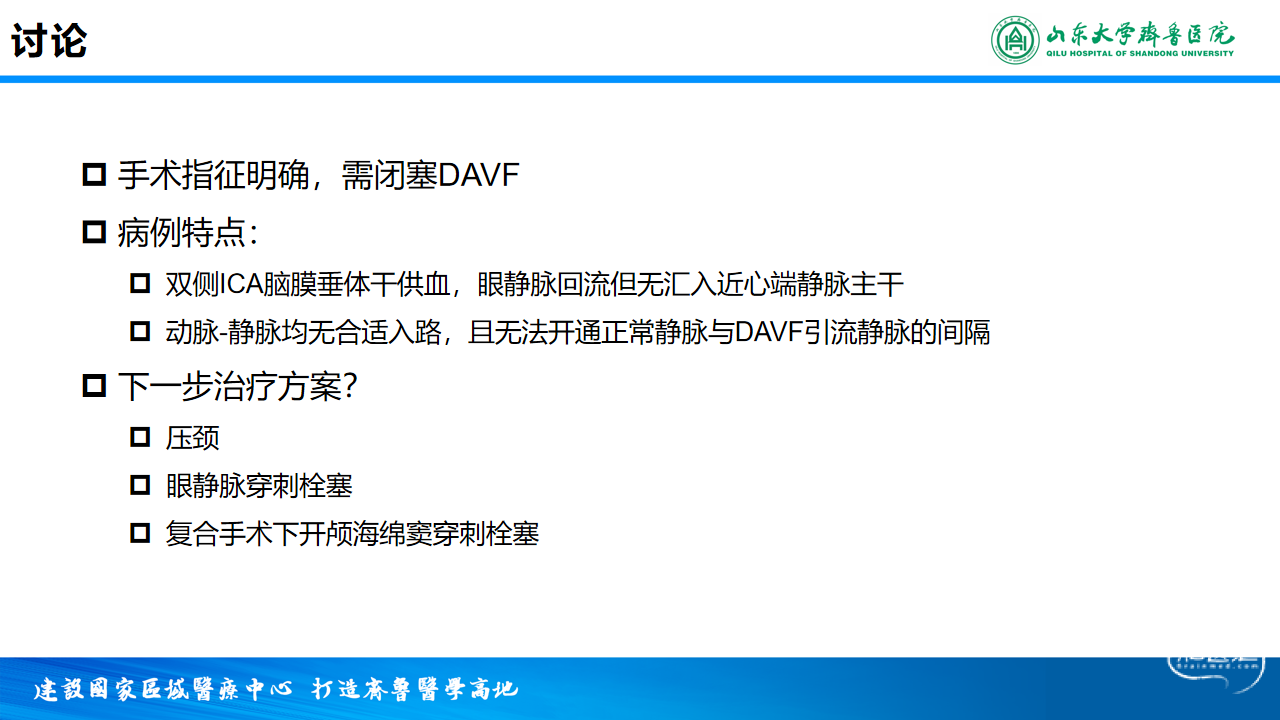

诊断:左侧海绵窦区硬脑膜动静脉瘘

手术指征:球结膜水肿严重,影响视力、感染风险高

病例特点:双侧ICA脑膜垂体干供血,眼静脉回流但无汇入近心端静脉主干

手术方案:静脉入路左侧海绵窦区硬脑膜动静脉瘘栓塞术

手术方案:静脉入路左侧海绵窦区硬脑膜动静脉瘘引流开通并栓塞术

手术难点:开通正常静脉与DAVF引流静脉的间隔

器械耗材:微导丝(PT / PILOT50 / 150)、微导管、ONYX-18等